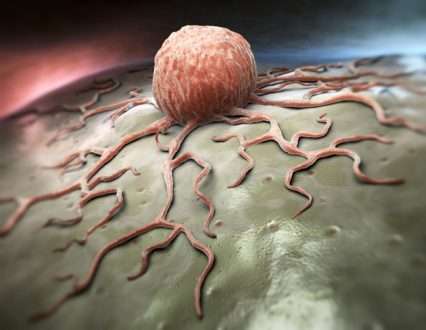

پروتئین BUB1 و فعالیت کیناز آن ممکن است فعال سازی EGFR را تنظیم کند

یک مقاله تحقیقاتی جدید در سالخورده (فهرست شده توسط MEDLINE/PubMed به عنوان “Aging (Albany NY)” [...]

بینش جدید در مورد اینکه چگونه سلول های دندریتیک سلول های T را برای مبارزه با بیماری مسلح می کنند

به عنوان بخشی از سیستم ایمنی، سلول های دندریتیک برای مبارزه با سلول های بدن [...]

مهندسی سلول های T برای از بین بردن سلول های سرطانی در درمان برخی از [...]

پروفایل تک سلولی نشانگر سلول ایمنی و تنظیم کننده ایمنی ضد تومور را نشان می دهد

تصور می شود که سلول های B نقش مهمی در ایمنی ذاتی و تطبیقی دارند، [...]